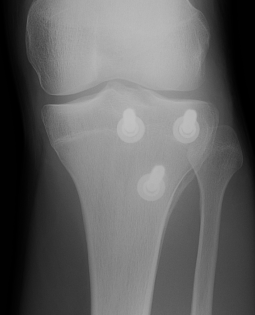

Ogden Classification

A: Undisplaced

B: Displaced

| Type I | Type II | Type III | Type IV |

|---|---|---|---|

| Avulsion distal tibial tubercle | Extension into tibial physis but not into knee joint | Extension across tibial physis and into knee joint | Extends posteriorly across tibial physis |

| Disrupts extensor mechanism | Disrupts extensor mechanism |

Disrupts extensor mechanism Disrupts articular surface Disrupts growth plate |

Disrupts extensor mechanism Disrupts articular surface Disrupts growth plate |

|

Associated Osgood-Schlatter Second most common |

Most common Risk of compartment syndrome |

Risk of compartment syndrome |

Type IB

Type IIB

Type III

Comminuted Type III